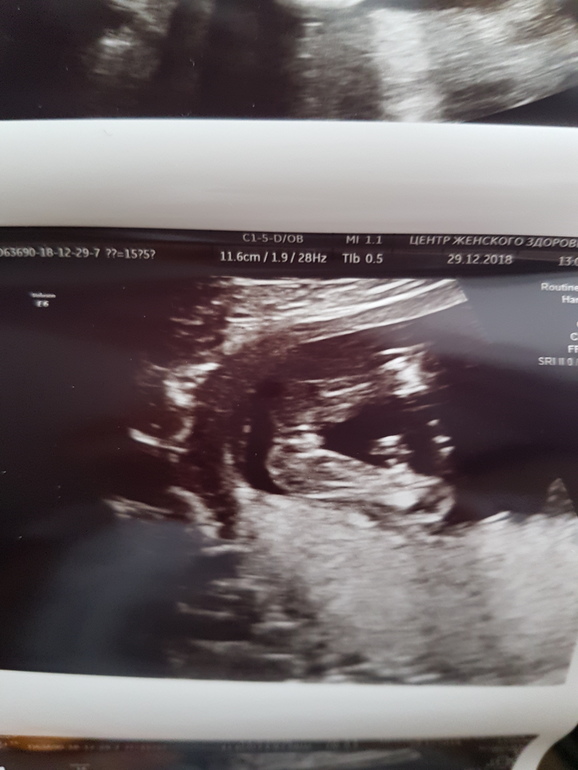

И всё. Хожу, смотрю на фото точно там Она или отрастёт ещё? Покажу два фото, но с одного ракурса. Кто что скажет? Вот честно, я такого ещё ни разу не видела, в 16 недель девочки такие?

Оооо! У нас такой же пирожочек на УЗИ было видно))) Поздравляем с доченькой💐🎉🎈

Ура:)) Вчера показала фото свекрови, она яички там нашла. Села, почитала комментарии опять, отпустило:))

Нету там никаких яичек))) ну предположим это яички. Тогда где сам писюн?😄спрятался)) неееее. Не сомневайся даже. Это точно девочка. У мальчиков по другому там😉

Спасибо тебе, голос разума:)) Я тоже помню Влада в 16 недель, там всё сразу было видно, высматривать не приходилось, а в этот раз слишком мнительная